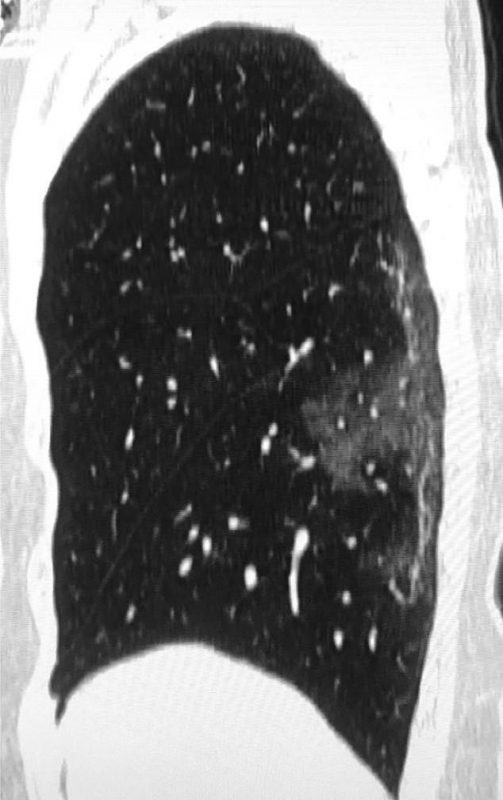

Scans show white patches in the lower areas of the lungs. Radiologists indicate those white patches ground glass opacity, a partial filling of air spaces.

The extended white patches were also identified with Middle East respiratory syndrome (MERS) and severe acute respiratory syndrome (SARS).